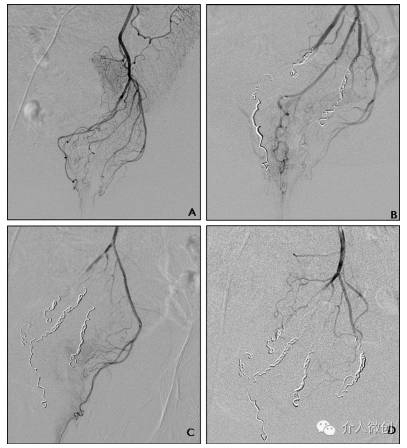

对可能引起痔疮的直肠上动脉分支进行了栓塞